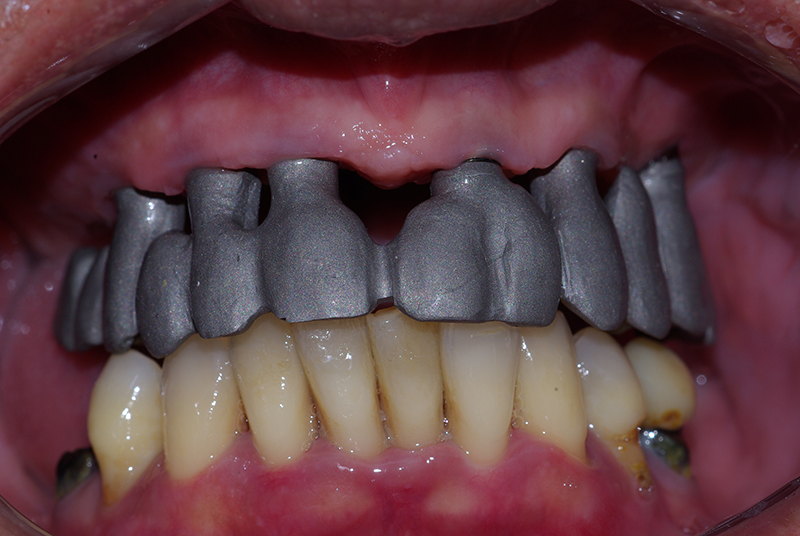

Tecnologia CAD CAM para Maior Precisão e Conforto

Utilizamos a tecnologia CAD CAM, um sistema avançado que possibilita a confecção precisa das próteses dentárias diretamente sobre os implantes. Esse método inovador garante um ajuste perfeito, um resultado estético superior e proporciona muito mais conforto e durabilidade. Com o CAD CAM, nossos pacientes contam com um processo mais rápido e previsível para alcançar o sorriso desejado.